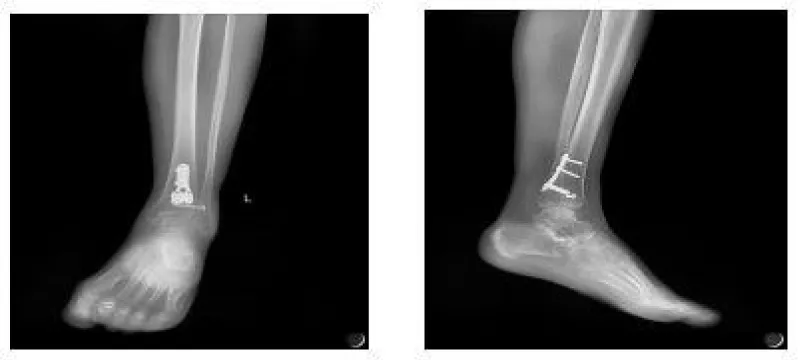

The anesthetic for the operation was lumbar anesthesia. A posterolateral approach was used to expose the Volkmann fracture. An anterior tibial approach was used to expose the Tillaux-Chaput fracture. The inferior tibiofibular joint was checked carefully. Fractures were reduced and then fixed. Volkmann fracture was fixed by buttress plate, and Tillaux-Chaput fracture was performed by hollow screw. Hook test intraoperative was negative. Anatomical reduction and perfect stability were confirmed by X and CT postoperatively (Figures 6.7). CT scan in the transverse section confirmed that the anterior and posterior edge of the distal fibula is in an arc with the fractures of the tibia. It meant there was no dislocation of the distal fibula. The anterior and posterior ligaments of the inferior tibiofibular ligament are in good condition.

Three weeks after surgery, the patient is required to touch down weight-bearing in a plaster splint. Patients are then allowed partial weight-bearing after six weeks and progress to weight-bearing. Ankle joint function exercises can be done three weeks after surgery. X noted that the fracture healed without shortening or rotation of the fibula when twelve weeks after surgery (Figure 8). The AOFAS score is 92 at twelve weeks follow-up [7,8].